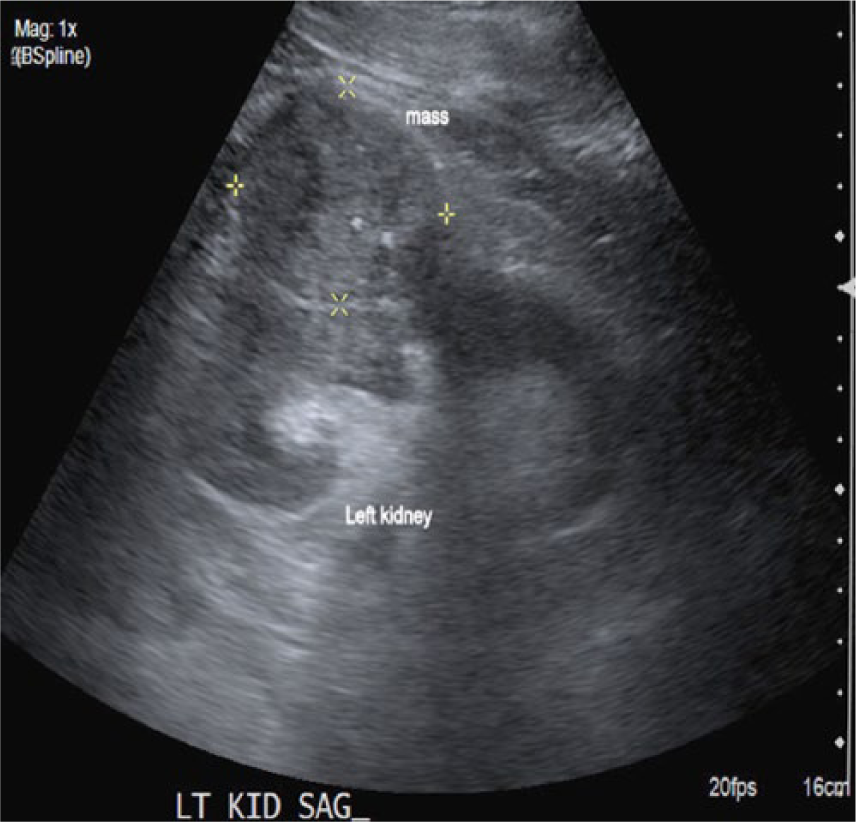

An elderly man in his early seventies was referred to the hospital as an outpatient to undergo an abdominal aortic aneurysm (AAA) screening. The patient had a history of smoking for 20 years. The sonographic examination was performed on an Acuson 2000 ultrasound system (Siemens, Washington, DC), with a curved array C5-2 probe (2-5 MHZ bandwidth). Sonographic findings showed no evidence of an AAA. Velocities and Doppler waveforms throughout the abdominal aorta were normal and showed no significant stenosis. During the examination, the sonographer observed echogenic material in the area of the inferior vena cava (IVC). Upon further examination, the IVC appeared to be thrombosed (Figures 1 and 2). Color Doppler imaging was used to confirm that the IVC was partially obstructed (Figure 3). A transverse view of the IVC and aorta also showed a thrombus in the left renal vein (Figure 4). This prompted the sonographer to extend the examination to the left kidney where a partially exophytic mass located on the anterior/superior portion of the left kidney was seen (Figures 5 and 6). The mass measured 5.43 cm long, 5.31 cm wide, and 4.30 cm anterior-posterior (AP) dimension. Color Doppler imaging showed significant vascularity within the mass (Figure 6). The findings were suspicious for renal cell carcinoma, and the patient shortly thereafter had additional testing with a computed tomography (CT) scan of the abdomen and pelvis with contrast. The CT scan confirmed a mass in the left kidney with direct tumor extension into the left renal vein. A thrombus was seen in the IVC both above and below the level of the renal veins. However, it could not be determined by imaging if the thrombus was related to bland thrombus rather than tumor thrombus. Also noted in the CT findings were prominent venous collaterals in the retroperitoneal region centrally and on the left. The patient had a complete left nephrectomy, and the placement of an IVC filter was also performed. The pathology report confirmed a 6.0 cm multifocal renal cell carcinoma with a large tumor extension into the left renal vein. The tissue histology using a hematoxylin and eosin stain showed a Fuhrman Grade 3 tumor, and the cancer was noted to be of a conventional clear cell type, which is the most common.

Longitudinal view of the left kidney. A partially exophytic mass is seen in the anterior/superior portion.